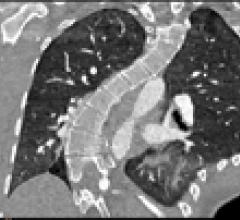

With headquarters in Tustin, Calif., Canon Medical Systems USA Inc. markets, sells, distributes and services radiology and cardiovascular systems, and coordinates clinical diagnostic imaging research for all modalities in the United States. Canon Medical Systems Corporation, an independent group company of Canon Inc., is a global leading provider of diagnostic imaging systems including CT, MRI, Ultrasound, X-ray systems and clinical laboratory systems. In business for more than 100 years, Canon Medical Systems Corporation (formerly Toshiba Medical Systems Corp.) was built to improve the quality of life for all people. It delivered on this mission with medical innovations that are “Made for Life”—made to improve the lives of patients, clinicians and administrators. Its legacy was built with pioneering medical technology, such as the world's first X-ray machines in 1932 and Japan's first magnetic resonance imaging (MRI) systems in 1983. Canon Inc. entered the healthcare business in 1940 with the development of Japan’s first indirect X-ray camera which was used for the early detection of pulmonary tuberculosis. The partnership of Toshiba Medical Systems Corporation and Canon (now Canon Medical Systems Corp.) brings together two cutting-edge technology businesses, founded with similar values of creativity, flexibility and patient-friendly healthcare solutions. Today, their combined history of research and innovation drive forward Canon Medical Systems’ vision for building a world-class healthcare enterprise. For more information: https://us.medical.canon/

Canon Medical Systems’ offering includes: computed tomography, magnetic resonance, ultrasound, X-ray, cath and EP lab